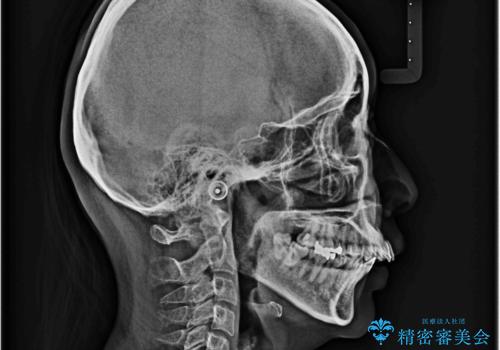

上顎前歯の突出を軽減 インビザラインによる抜歯矯正

- 上の前歯の突出感を気にして来院された患者様です。

目立たない装置を希望とのことで、上顎左右第一小臼歯を抜歯し、インビザラインにて矯正治療を行うこととしました。

インビザラインにて抜歯矯正を行うと、高頻度で奥歯が咬み合わなくなります。

また、抜歯スペースに向けて奥歯が移動する際、必ず傾斜して移動するため、仕上がりの咬み合わせはワイヤー矯正と比べて明らかに劣ります。